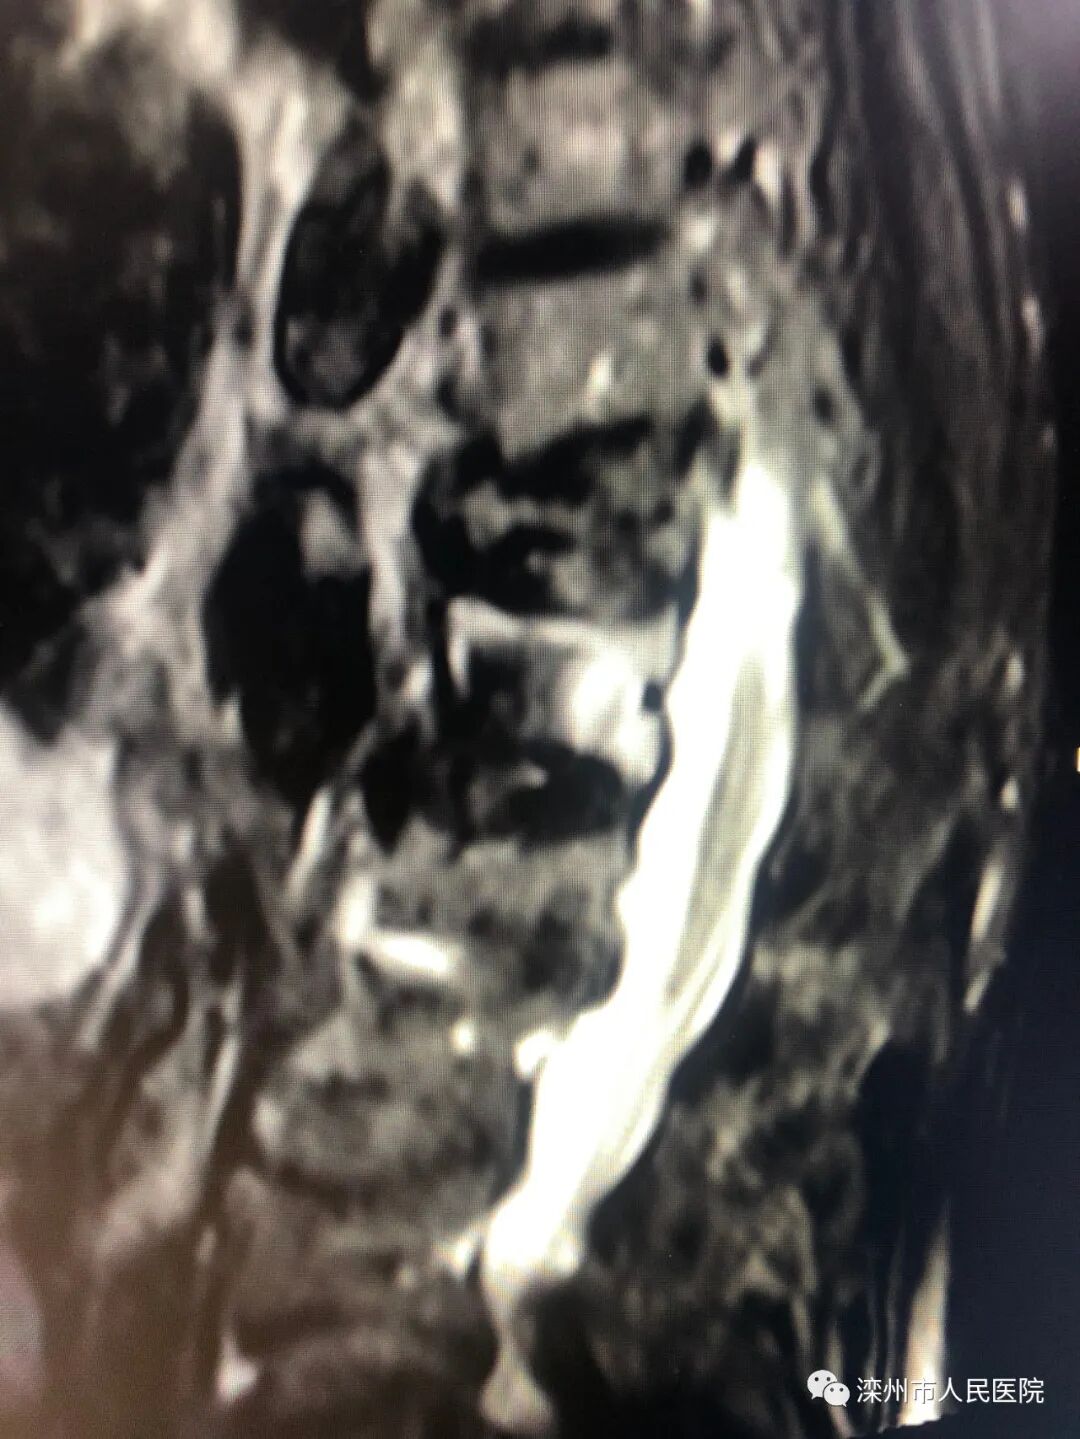

(术前核磁:白色的为新鲜骨折的椎体)

患者秦某某既往多段胸腰椎压缩骨折,脊柱后凸畸形,此次胸7-胸10压缩骨折,患者张某某高龄。两位患者如卧床保守治疗可引起压疮、深静脉血栓、坠积性肺炎及心脑血管意外等严重并发症,任何一种情况都可能是致命的。